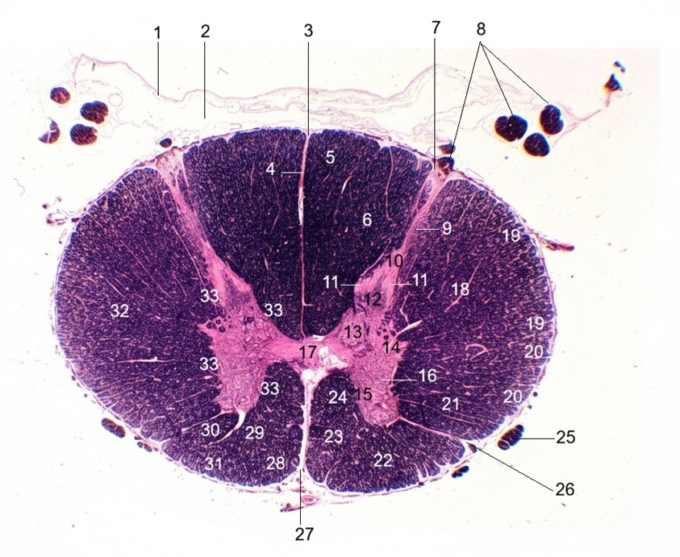

1. Arachnoid membrane

2. Subarachnoid space

3. Dorsal median sulcus

4. Dorsal median septum

5. Gracile fasciculus

6. Cuneate fasciculus

7. Dorsolateral sulcus

8. Dorsal root

9. Dorsolateral tract of Lissauer

10. Dorsal marginal nucleus (Lamina I)

11. Substantia gelatinosa (Lamina II)

12. Nucleus proprius (Lamina III, IV)

13. Nucleus dorsalis of Clarke

14. Intermediolateral nucleus and lateral horn

15. Medial motor nuclei (Lamina IX)

16. Lateral motor nuclei

17. Central canal with central gray matter